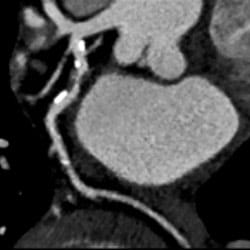

Coronary computed tomography angiography (CCTA) is a noninvasive heart imaging test that generates three-dimensional (3D) images of your heart, coronary arteries and great vessels.

During the test, you will receive standard iodine-containing contrast material as an intravenous (IV) injection to help obtain better images. The scan is acquired seconds after the contrast is administered, in which x-rays pass through the body and are sensed by detectors in the scanner to produce high-quality 3D images.

If more details are needed to assess your coronary arteries, a HeartFlow analysis may be ordered. This analysis uses your CCTA scan (no additional imaging required) to provide further information for your doctor.